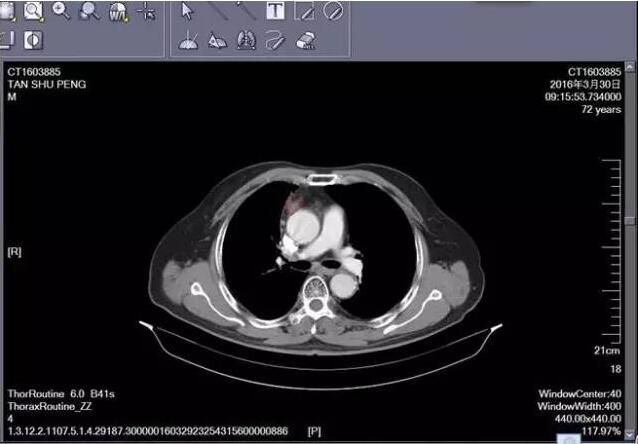

下面這張是今年三月復查的CT,腫塊繼續(xù)縮小,患者一般狀況可,無特殊不適。